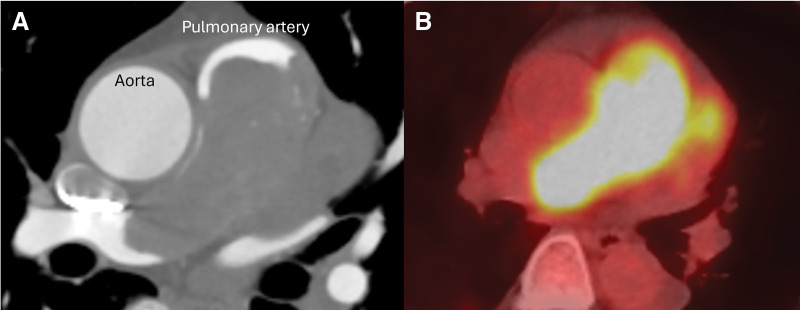

Case presentation: A 64-year-old woman, complaining of dyspnea for a month, was referred for a pulmonary artery tumor. Imaging studies confirmed an intraluminal tumor that obstructs the pulmonary artery trunk and extends to the right ventricular wall and interventricular septum, suspecting a malignancy. During preoperative workups, she developed acute hemodynamic and respiratory deterioration due to pulmonary embolization, so emergency surgery was planned on a salvage basis. The tumor originated from the pulmonary artery intima just distal to the pulmonary valve, obstructed the pulmonary artery trunk, and extensively involved the left main coronary artery and the interventricular septum, where complete resection of the tumor was not achieved. Reconstruction of the pulmonary valve, the right ventricular outflow tract (RVOT), and bilateral pulmonary arteries were performed using a composite of a prosthetic valve and vascular grafts. The patient's postoperative course was uneventful, and she was discharged home asymptomatic. Pathological diagnosis of the operative specimen confirmed pulmonary intimal sarcoma. After 4 months of postoperative chemotherapy, tumor progression was confirmed. The patient passed away at home 8 months after surgery.